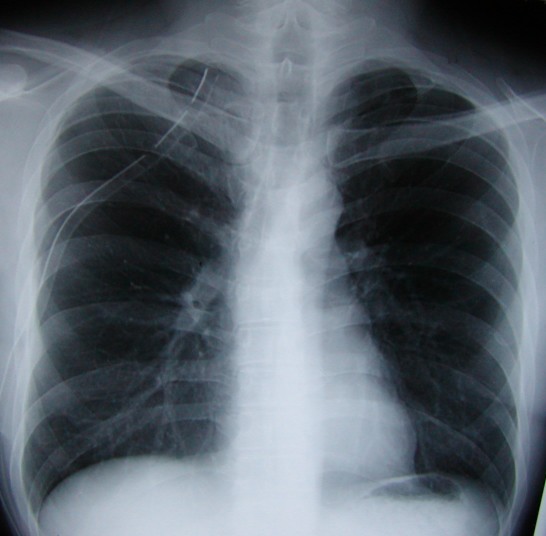

向かって左側の胸腔(右肺)にドレーンを残置して脱気したため、肺が膨らんでいます。

左の胸腔内を左下から鎖骨の上までドレーンが伸びているのが分かります。

12月2日の手術後のドレーンのため目一杯上の方まで入っています。

写真−1と比べると肋骨がスッキリ写っていた部分が白っぽくなり、肺が膨らんだことがわかります。